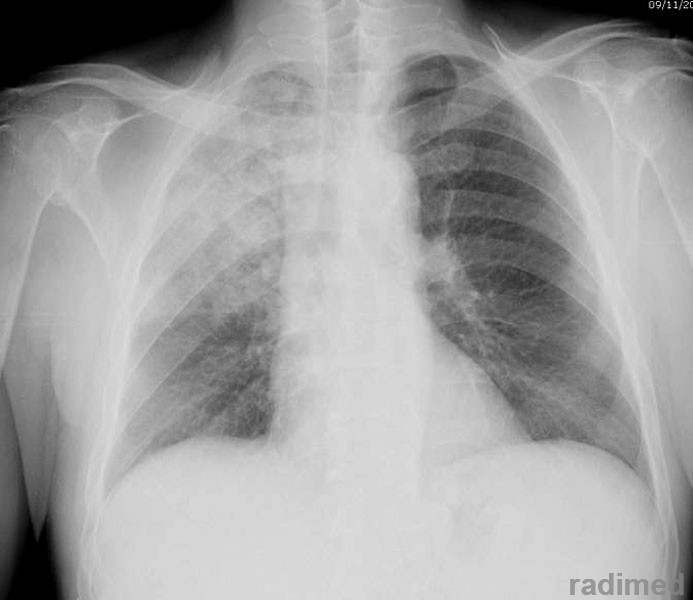

Nuevas guías para neumonía intrahospitalaria proponen acortar la duración del tratamiento

- Neumonología